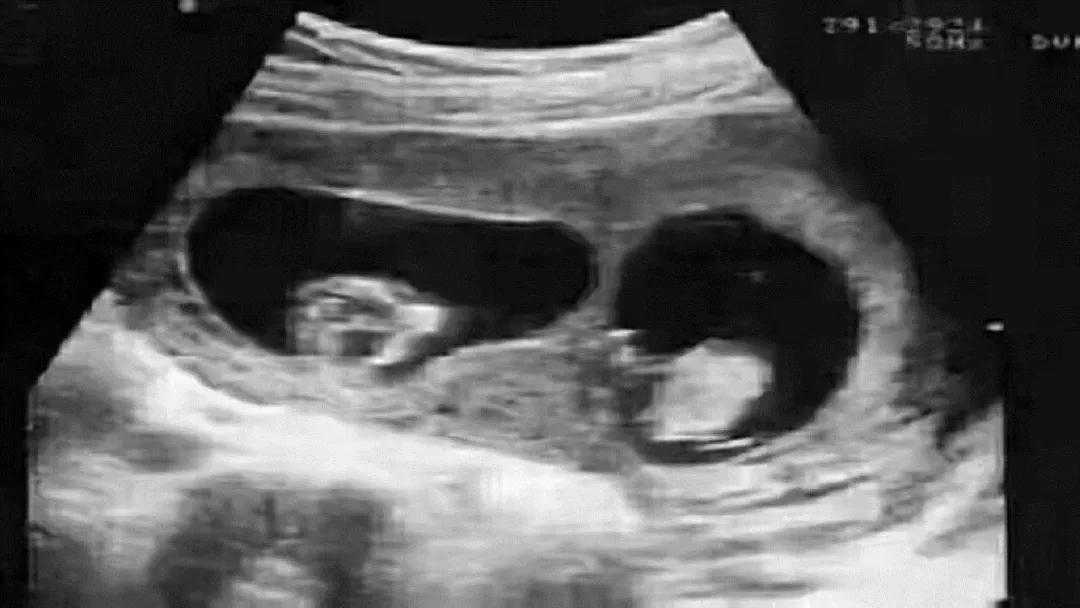

小李和小黄结婚多年,但始终没有成功怀上宝宝。随着年龄越来越大,最终选择了做试管婴儿。可喜的是这次倒是成功了。生下来个大胖小子,全家也很欢喜。

鉴定结果显示,孩子是妈妈生的没错,但父亲却不是小黄,通过对比来说,最大概率的可能是叔叔。不过问题又来了,偏偏小黄是个独生子,这又是哪来的叔叔呢?

广医三院法医物证司鉴所马晓燕:这可能就遇到了鉴定行业中非常罕见的嵌合体案例,也就是说,这位“爸爸”身体内携带有两个人的DNA,可能他在妈妈肚子里的时候,还有一个双胞胎弟弟,但是这个双胞胎弟弟的胚胎没有发育下来,反而和他的胚胎出现了融合,导致这个“爸爸”携带两个人的DNA出生,而且他把弟弟的DNA传给了孩子。

嵌合体其实也称为“奇美拉”现象。奇美拉原本指的是希腊神话中,一种狮头,羊身蛇尾的怪物,可以参考中国的四不像。而嵌合体正是一个人的体内含有多组DNA的现象,也可以通俗的理解为两个受精卵融合成一颗的现象。科学家认为这个发作概率大概在10%-15%。

二,为什么会有嵌合体现象?首先嵌合体的现象也仍在研究中,但是大概是以下几种。第一种就是和上文的事例一样,属于双胞胎在发育过程中,另一个抢不过对方,从而导致被“吞噬融合”,只能留下一部分DNA了。不过这也不要觉得残忍,算是生命的一种优胜劣汰吧,毕竟双胞胎原本对营养、空间等方面有更多需求,属于是无意识的行为吧,当然这是比较少见的情况。毕竟全世界这种被报道出来的,不超过100例。